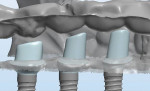

The patient agreed, and 4/3 mm x 11.5 mm Certain® PREVAIL® Implants (Biomet 3i, www.biomet3i.com) were placed as planned. BellaTek® Encode® Healing Abutments (Biomet 3i) were placed on the implants. The dimensions of each abutment were 3.4 mm (prosthetic diameter) x 5 mm (abutment profile) x 3 mm (abutment height). The gingival flaps were repositioned and secured using a continuous 4.0 chromic gut suture.

Following 3 months of healing, all the implants were found to be healing well (Figure 1). At least 1 mm of the abutments were exposed above the gingiva circumferentially. The tightness of the BellaTek Encode Healing Abutments was verified using a 0.048 hex hand driver, and radiographs confirmed that the abutments were completely seated (Figure 2). Full-arch impressions of both arches were made, using trays filled with medium-body polyether impression material (Impregum™ F, 3M ESPE, www.3MESPE.com). Light-body polyether impression material (Permadyne™, 3M ESPE) was syringed around the healing abutments. The impressions were inspected for defects in the area of the healing abutments (Figure 3). A softened wax was used to make an occlusal registration. These records were sent to the dental laboratory with a completed lab prescription.

The dental laboratory placed BellaTek Encode Healing Abutments that were the same dimension as those used in the impression on implant analogs. The abutments and analogs were placed in the impression, and silicone (Gi-Mask, COLTENE, www.coltene.com) was injected around them to aid in the fabrication of a soft-tissue model. The dental laboratory then removed the implant analogs and abutments and poured die stone to complete the master cast, void of any bubbles (Figure 4). The lab mounted the casts on a Stratos 100™ articulator using Adesso Split Plates (Ivoclar Vivadent, Inc., www.ivoclarvivadent.com ).The lab filled out a prescription and sent the models without the articulator to the BellaTek® Production Center in Florida.